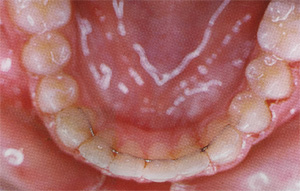

C'est un appareil (un peu comme un protège dents de boxeur), réalisé sur mesure, qui maintient et l'alignement des dents sur leur arcade ET le placement des mâchoires l'une par rapport à l'autre permettant ainsi une bonne occlusion. Les mâchoires sont bloquées dedans, ce qui limite sa durée. On le porte principalement la nuit. Il est normal que les premiers jours, l'appareil fasse un peu saliver. Cela cesse rapidement.